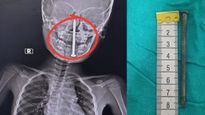

जब खेल-खेल में बच्चा निगल ले दवा या सिक्का, तो क्या करें और क्या नहीं?